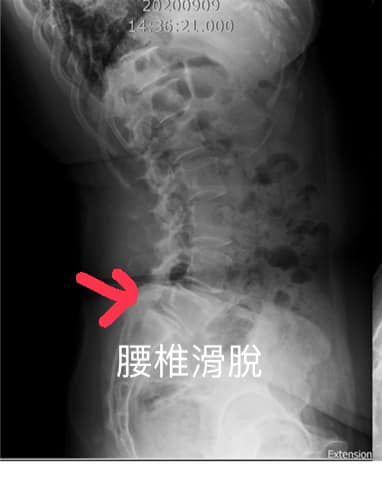

Cervical Spine Treatment Cases 腰椎治療案例 #腰椎手術失敗綜合症候群 #術後沒保養還是又繼續椎間盤突出 #感謝台北梁小姐熱情見證 ... 2021.03.02 #超感動醫案感謝中壢姚阿姨見證 #原本已經坐輪椅的人生看到一絲希望 #脊刻救援牛轉乾... 2021.02.22 #感謝新北中和區陳大哥熱情見證 #從北到南看過眾多中西醫民俗療法 #腰痛到連躺跟坐都... 2021.02.17 #感謝桃園龜山蘆先生熱情見證 #腰椎跟屁股痠痛超過十二年 #腰椎纖維環裂隙導致神經根... 2021.02.16 #騎馬摔傷腰椎醫案 #感謝內湖陳先生熱情見證 #椎間盤突出合併輕微椎間孔狹窄 #重新騎... 2021.02.03 #巨大椎間盤突出醫案 #脊椎整合中醫微創逆轉勝 #感謝三峽林先生熱情見證 #為何突出的... 2021.01.29 #腰椎粉碎性骨折手術後調養醫案 #坐輪椅的人生終於看到希望 #脊椎手術失敗症候群 #Fai... 2021.01.26 #感謝台中市大肚區患者熱情見證 #第二次治療腰痛好超多 #腰酸痛時間快一年了 #親筆寫... 2020.12.05 #腰椎嚴重滑脫醫案 #原本左腳麻痛無法久站超過十分鐘 #脊椎整合中醫微創療法逆轉勝 #... 2020.12.02 #感謝林口楊先生熱情見證 #椎間盤整和中西醫微創療法逆轉勝 #曾經大痛到無法走路嚴重... 2020.11.25 #今天來聊巨大骨刺為何可以吸收回去! #椎間盤突出需要多久才能吸收呢? #馬尾神經症候... 2020.11.10 #腰椎滑脫一定要開刀嗎? #骨科認為開刀置放骨釘穩定錐體 #如果患者可以藉由增強肌... 2020.11.04 #六年的長期腰酸痛醫案 #原來是椎管狹窄合併輕微突出 #每年冬天準時發作苦不堪言 #感... 2020.10.31 #椎管狹窄案例 #感謝新莊陳大哥熱情見證 #腰酸痛數年原來是椎管狹窄 #來診前已經痛到... 2020.10.28 #知名四代魚丸店掌門人熱情見證 #腰椎中醫微創逆轉勝 #椎間盤突出醫案 #感謝新北... 2020.10.23 ← 上一頁 8 9 10 11 12 下一頁 →